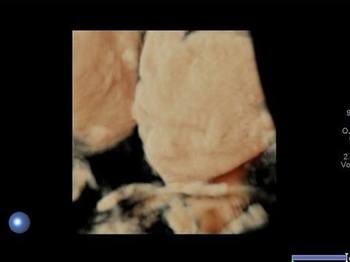

Parotis yüzün her iki yanında, kulak deliklerinin hemen iç kesiminde yüzeyde yerleşimli olarak izlenen tükürük bezleridir. Bu tükürük bezleri içerisinden önemli damar yapılar ve yüzün en nemli siniri olan fasial sinir geçer.